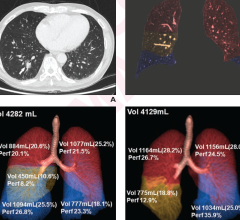

Nov. 8, 2024 — Lunit has announced new research findings demonstrating the potential of its artificial intelligence (AI) ...